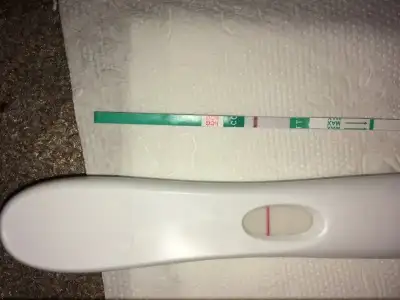

Amin canım sağol allah raZı olsun darısı sizlerin başına en kısa zamanda inşallah evet artık yanılıyor olamazlar :)Canimmm artik kesin hamilesin allahin izniyle bunca test yanılıyor olamaz kuzum. Çok sevindim coook. Bize de umut oluyorsunuz böyle ne guzel yaaa rabbim saglikla kavusmak nasip etsin